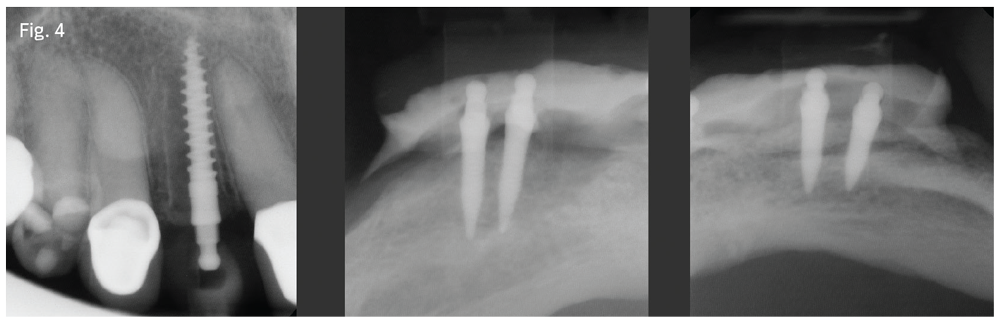

Figure 3 Dentaltown Magazine

Figure 4

Visit #1: We gathered all diagnostic data—full-mouth radiographs (Fig. 1), preop photos (Fig. 2), CBCT scan (Fig. 3) and study model impressions. The patient was mildly sedated—30 milligrams of hydroxyzine slurry swallowed and 0.125mg triazolam crushed sublingually—and monitored with pulse oximeter throughout the treatment phase of the appointment.

After using Carbocaine 3% non-epinephrine local anesthetic to anesthetize the patient, I performed an atraumatic extraction for tooth #7, placed a 2.5-by-15mm implant (Fig. 4) and fabricated a temporary crown. I then switched my attention to the lower arch.

The patient's mandible was so resorbed that her lower denture did not fit in any usable way. I placed four mini-dental implants (2 by 10mm) with O-ball attachments (Fig. 4). I then cut away the posterior segments of the existing denture, leaving only the anterior six teeth to be used as a temporary, and processed the housings for the four mandibular implants into the anterior segment of the denture, using a self-cured denture base resin.